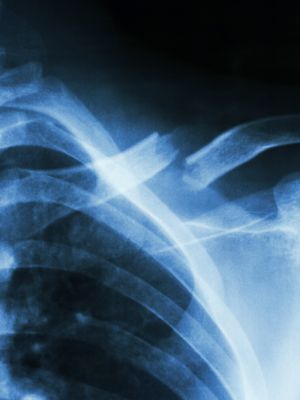

Osteoporoosi

Pahasti kaatunut Helena, 73: "Murtuneet kylkiluut ja nilkka paljastivat osteoporoosin"

Tiesitkö? Osteoporoosi voi murtaa selkänikaman huomaamatta

Laske luidesi murtumariski helposti

Miehen luukato: Näin tunnistat osteoporoosin riskit

Nyt ei kannata kaatua!